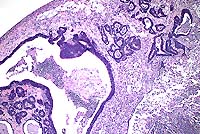

Case I - ABBOTT-02 (AFIP 2595736)

Signalment: 26- to 30-month-old, male, Long-Evans, rat.

History: The rat was euthanized with a history of weight loss occurring over several weeks. This rat had not been used on any study.

Gross Pathology: A tan mass filled the lumen of a 1 cm segment of colon. Adjacent to this area, the serosal and mesenteric fat contained several coalescing, firm, cream-colored to gray nodules up to 1 cm in diameter.

Contributor's Diagnosis and Comments: Adenocarcinoma, colon, rat.

Spontaneous carcinomas of the small and large intestine are reported to be rare in rats. References disagree regarding the most common site of origin, and the most common site may differ in different strains and stocks. In this Long-Evans rat, there was transmural invasion of the neoplasm through the colonic wall with subserosal abscess formation, but metastases were not observed.

Case 5-1. Colon. Shows subserosal, colonic adenocarcinoma with cyst and abscess formation. 4X

AFIP Diagnosis: Colon: Adenocarcinoma, colonic, Long-Evans rat, rodent.

Conference Note: There was considerable variation in the slides distributed for this case. Several slides viewed in conference demonstrated minimal or no invasion of neoplastic cells into the tunica muscularis, and no neoplastic cells were present in the subserosal abscess. This led some participants to a diagnosis of atypical hyperplasia or carcinoma in situ. However, in other slides, invasive growth indicative of malignancy is evident.